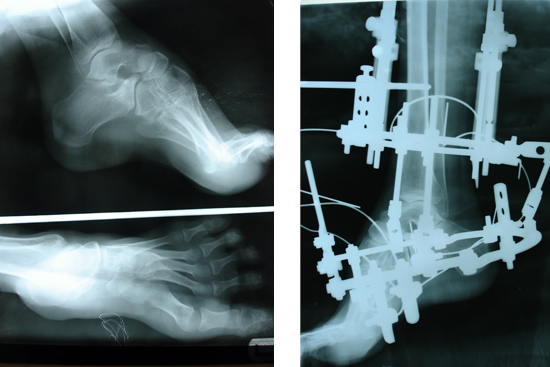

TEV

Management Of Neglected Tev